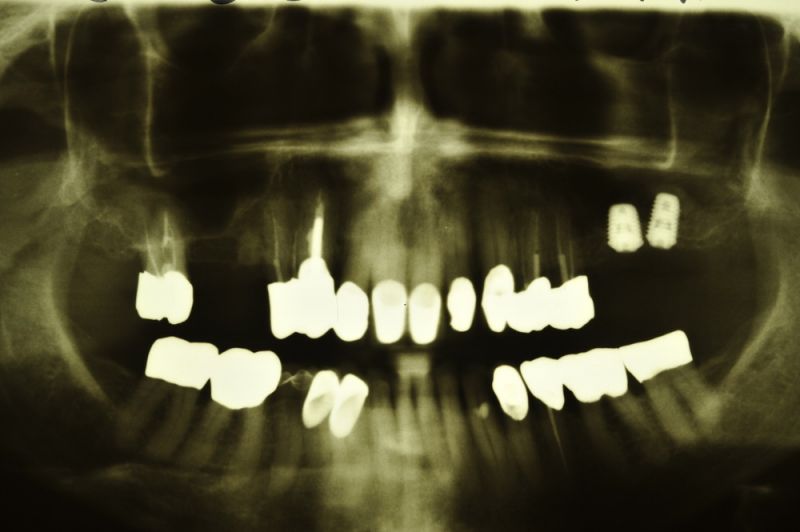

76 jährige Patientin aus Kiel zur Zahnentfernung im Oberkieferseitenzahnbereich

Aus parodontalen Gründen mussten bei der Patientin im Oberkieferseitenzahnbereich mehrere Zähne entfernt werden. Auf der rechten Seite wurden bereits zwei Implantate, mit einem externen Sinuslift verbunden, gesetzt.

Heute wurden die Zähne 15 und 17 entfernt. An Zahn 15 erkennt man ein großes Granulom, im Sinne einer chronischen Entzündung, um die Wurzelspitze herum. Dieses Granulom hat der Patientin keinerlei Beschwerden verursacht. Der Zahn hätte aber so nicht gehalten oder versorgt werden können, weil dieses Granulom die Tendenz hat sich weiter zu vergrößern und dabei Knochen einzuschmelzen, der wiederum für den Halt der Zähne benötigt wird.

So sehen Granulome aus, die sich an und um die Wurzelspitzen chronisch beherdeter Zähne gebildet haben.

In aller Regel sind diese Zähne sehr lange Zeit vollkommen beschwerdefrei und erst im Rahmen röntgenologischer Untersuchungen werden derartige Befunde offenbar.